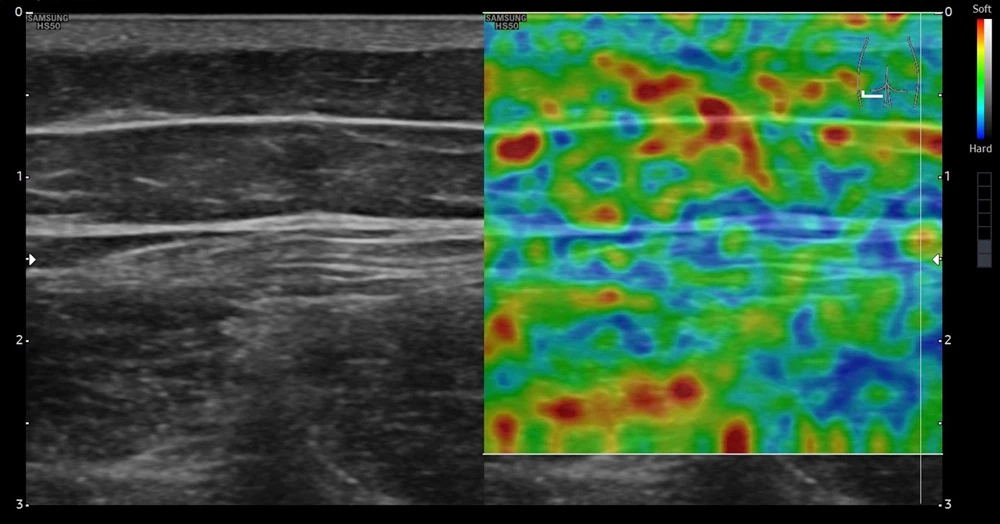

Эластосканы пациента после окончания лечения. Левая сторона

После курса лечения у пациента в тех же исследуемых участках при поверхностном сканировании в тех же точках наблюдалась значительно более высокая жесткость ткани (на снимках окрашены в синий и зеленый цвета).

Отмечается увеличение прочности на границе кожи и подкожной клетчатки.